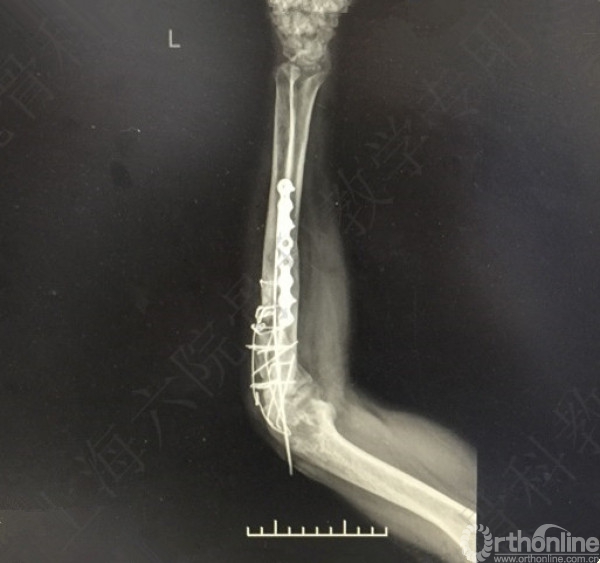

患者左尺桡骨多发骨折伴肘关节脱位,术后2年,桡神经损伤,左拇指伸受限。

X线及CT示:左尺桡骨骨不连,尺骨力线差,成角,桡骨头脱位,创伤性关节炎。

患者择期行左尺桡骨取原内固定+切开复位内固定术+髂骨异体骨植骨+桡骨头切除术。

术后X线片示:左尺桡骨骨不连术后,对位对线可,内固定牢靠,桡骨头切除,肘关节在位。

医方第一次术后,未能纠正骨折力线,未发现桡骨头脱位,手术方式和操作欠妥当。存在对疾病评估不足,漏诊,手术方式不当,手术操作不当,术后并发症观察及处理不当等过失。